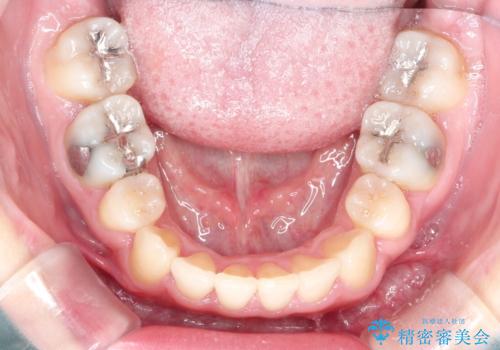

左上の犬歯が通常の位置より、かなり上方にあり、乳歯の残存と前歯のがたつきがありました。

残った乳歯と上下左右の永久歯を1本ずつ抜歯して、ワイヤーにて矯正することとしました。